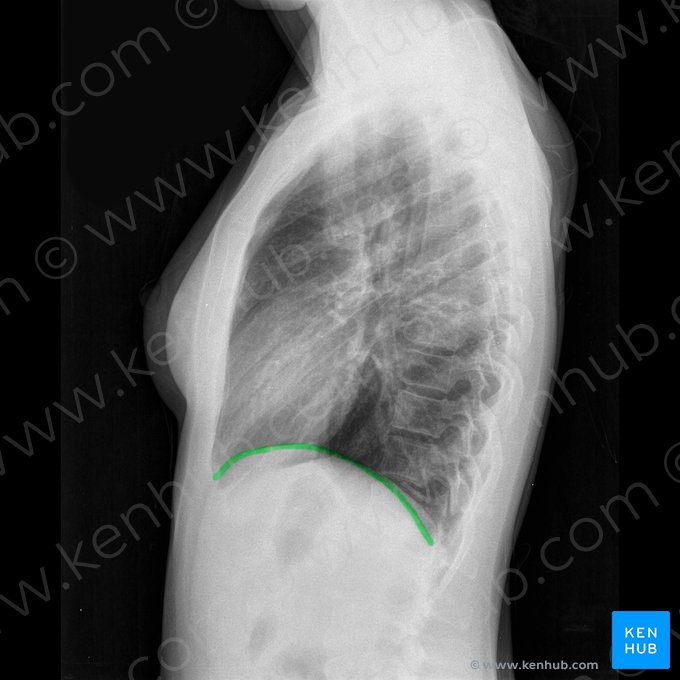

Diafragma

O formato do diafragma também pode fornecer muitas informações sobre o estado de saúde atual do paciente. Normalmente, o diafragma é curvo, e o hemidiafragma direito é mais alto do que o esquerdo, já que repousa sobre o fígado. Se o diafragma estiver achatado o paciente pode ter asma crônica ou doença pulmonar obstrutiva crônica (DPOC). É sempre importante buscar a presença de ar livre sob o diafragma, já que isso pode significar uma perfuração gástrica ou intestinal, e constitui uma emergência médica.

Margens, efusões e partes moles extratorácicas

Ao avaliar uma radiografia do tórax é também fundamental checar os recessos costodiafragmáticos nas margens do diafragma, já que o borramento dos recessos costodiafragmáticos (de forma que eles não são nitidamente identificados) pode estar relacionado a derrames pleurais (uma efusão líquida localizada entre a pleura e o tecido pulmonar). Derrames ou efusões pleurais nem sempre são óbvios, então é sempre importante procurar atentamente. Uma efusão posterior pequena pode ser vista mais facilmente em um filme lateral do que em um filme em PA.